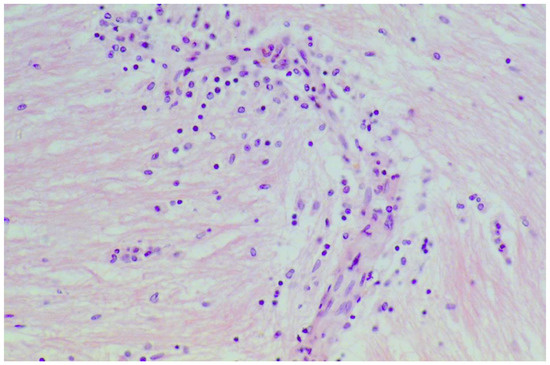

| Hadjivassiliou 2007, UK | 13 | Muscle | Internal nuclei; Basophilic rimmed vacuoles; fiber splitting; Endomysial chronic inflammatory cell infiltrate (CD3+ cells), Fibrosis |

| Hendriksson 1982, Sweden | 5 | Muscle | Basophilic sarcoplasm; Vesicular nuclei, Muscle Fibre Atrophy, Splitting & Internally placed nuclei |

| Danielsson 2017, Sweden | 13 | Muscle | Inflammatory infiltrates & muscle fiber degeneration |

| Hadjivassiliou 1997, UK | 2 | Muscle | Inflammatory myopathy & Basophilic rimmed vacuoles |